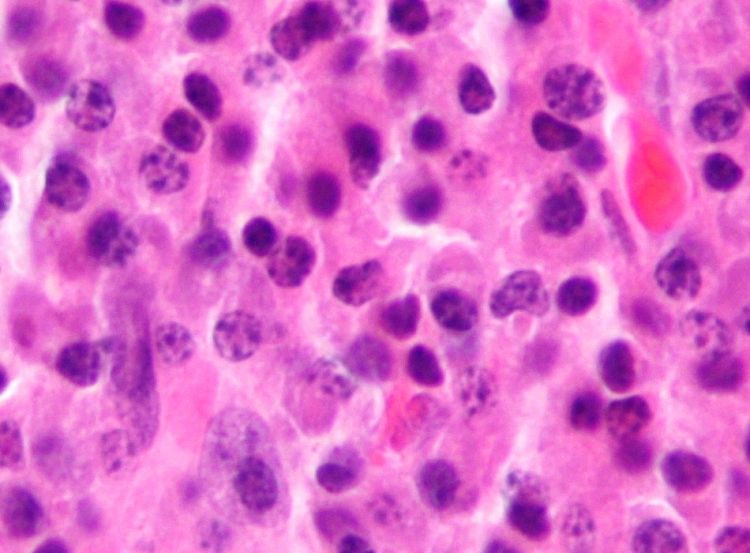

A patient advocacy organization quoted Natalie Callander, MD, professor (CHS), Hematology, Medical Oncology and Palliative Care, about an ongoing Phase I clinical trial of I-131-CLR1404 to allow targeted delivery of ionizing radiation to myeloma cells.

“We are excited to be developing a new treatment option for this difficult disease. Because of its unique mechanism of action, I-131-CLR1404 may represent an entirely different treatment approach for patients that are no longer responding to currently available therapies,” said Dr. Callendar.

The Phase I trial is being conducted at three myeloma centers. It is testing the best dose, safety and tolerability of I-131-CLR1404, with and without concurrent weekly dexamethasone. Myeloma patients must have been previously treated with (or have become intolerant to) an immunomodulator and a proteasome inhibitor.